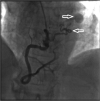

Coronary artery aneurysm is a relatively rare disorder that is usually discovered as a secondary finding in patients undergoing coronary artery angiography. Coronary artery fistulas are relatively more frequent than rare aneurysms and are often associated with other cardiac abnormalities. The etiology of aneurysms is mostly atherosclerotic, and they are less frequently associated with other acquired or congenital diseases, such as Kawasaki disease, connective tissue diseases, septic emboli, arteritis, and iatrogenic disease. We report a 70-year-old woman with a rare combination of a coronary artery aneurysm associated with a coronary artery fistula, which drained into the pulmonary artery. The diagnosis of our patient was made by selective coronary angiography and confirmed by computed tomography angiography. The patient was treated surgically because of the symptomatic course of the disease.